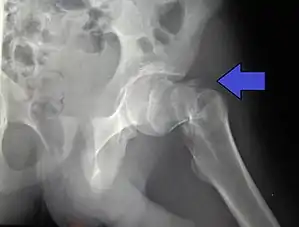

Intertrochanteric hip fracture in a 17-year-old male